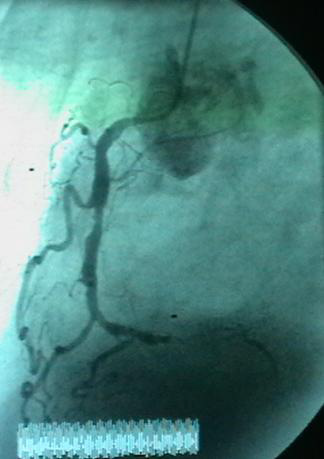

病例3:对角支开口病变

右斜+头位 支架定位

蜘蛛位支架定位

支架植入术后

看对角支病变采用蜘蛛位(Spide位)、右斜+头位

TAXCOR 2.5×13mm DES植入。此病例入选TAX.DE 研究

采用双导丝分别到LAD/第一对角支,因为LAD粗大,以防万一。

· 此病例注意一点:定位时支架近端标记(mark)在LAD内1mm(如图所示),mark位于LAD管腔中央。支架移动定位时,在造影下定位。